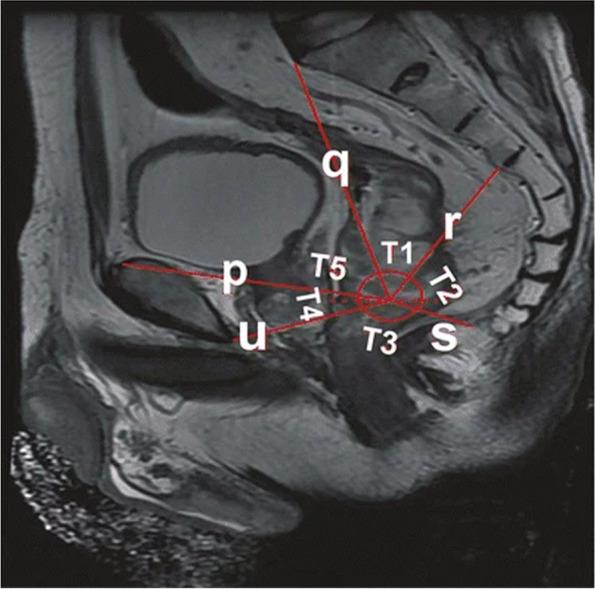

Advances in pelvic imaging parameters predicting surgical difficulty in rectal cancer.

Due to the fixed bony structure of the pelvis, the pelvic operation space is limited, complicating the surgical operation of rectal cancer, especially middle and low rectal cancer. The closer the tumor is to the anal verge, the smaller the operative field and operating space, the longer the operative time, and the greater the incidence of intraoperative side injuries and postoperative complications. To date, there is still no clear definition of a difficult pelvis that affects the surgical operation of rectal cancer. Few related research reports exist in the literature, and views on this aspect are not the same between countries. Therefore, it is particularly important to predict the difficulty of rectal cancer surgery in a certain way before surgery and to select the surgical method most suitable for each case during the treatment of rectal cancer.